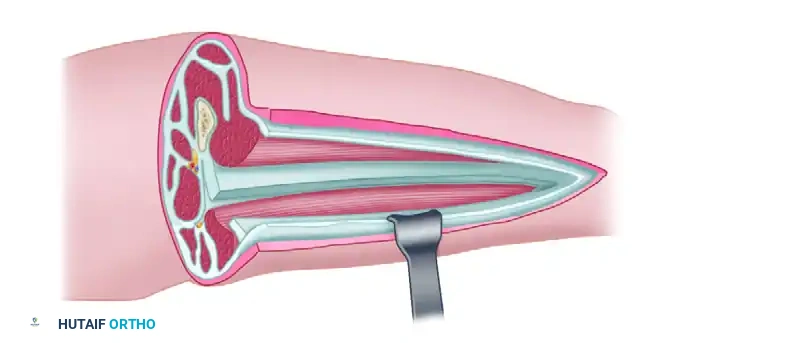

Surgical Technique: Four-Compartment Decompression (Davey, Rorabeck, and Fowler)

This technique utilizes a single, highly expansile lateral incision to access all four compartments of the lower leg. While a two-incision technique (anterolateral and posteromedial) is also widely accepted, the single lateral approach described by Davey et al. is highly effective when performed with precise anatomical knowledge.

Step 1: The Lateral Skin Incision

Make a generous lateral skin incision beginning proximally at the level of the fibular neck and extending distally to approximately 3 to 4 cm proximal to the lateral malleolus.

Step 2: Anterior and Lateral Compartment Release

Undermine the skin anteriorly to expose the fascia overlying the anterior and lateral compartments. Identify the anterior intermuscular septum dividing these two compartments. Perform a longitudinal fasciotomy of the anterior compartment, taking care to protect the superficial peroneal nerve, which exits the lateral compartment to become subcutaneous in the distal third of the leg. Subsequently, perform a longitudinal fasciotomy of the lateral compartment.

Step 3: Superficial Posterior Compartment Release

Undermine the skin posteriorly from the primary incision to expose the fascia of the superficial posterior compartment (containing the gastrocnemius and soleus muscles). Perform a longitudinal fasciotomy to release this compartment.

Step 4: Deep Posterior Compartment Release

This is the most technically demanding step. Develop the interval between the superficial posterior compartment and the lateral compartment. Identify the fibula. The flexor hallucis longus (FHL) muscle must be dissected subperiosteally off the posterior aspect of the fibula and retracted posteromedially. Once retracted, identify the deep fascial attachment of the tibialis posterior muscle to the fibula. Incise this fascia longitudinally to completely decompress the deep posterior compartment.